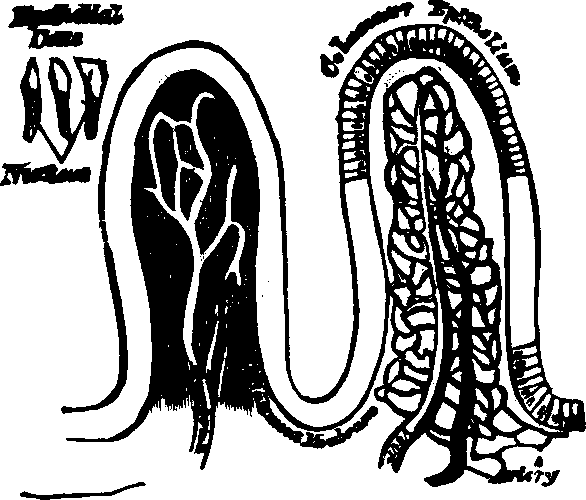

Fig. 30. Villi of the small

intestine greatly magnified.

Fig. 31. A section of the Ileum,

turned inside out, so as to show the appearance and arrangement of the

villi on an extended surface.

Fig. 35. Villi of the small

intestine greatly magnified.

Absorption is the vital function by which nutritive materials are selected and imbibed for the sustenance of the body. Absorption, like all other functional processes, employs agents to effect its purposes, and the villi of the small intestine, with their numberless projecting organs, are specially employed to imbibe fluid substances; this they do with a celerity commensurate to the importance and extent of their duties. They are little vascular prominences of the mucous membrane, arising from the interior surface of the small intestine. Each villus has two sets of vessels. (1.) The blood-vessels, which, by their frequent blending, form a complete net-work beneath the external epithelium; they unite at the base of the villus, forming a minute vein, which is one of the sources of the portal vein. (2.) In the center of the villus is another vessel, with thinner and more transparent walls, which is the commencement of a lacteal.